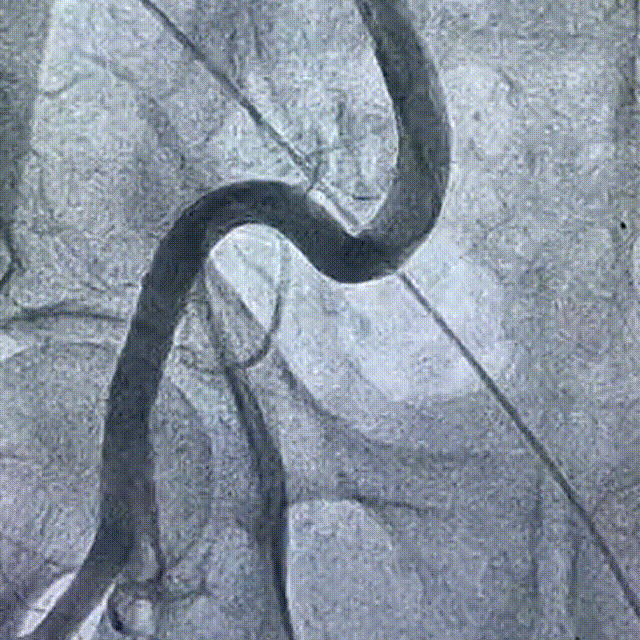

右侧股动脉造影

主动脉根部造影